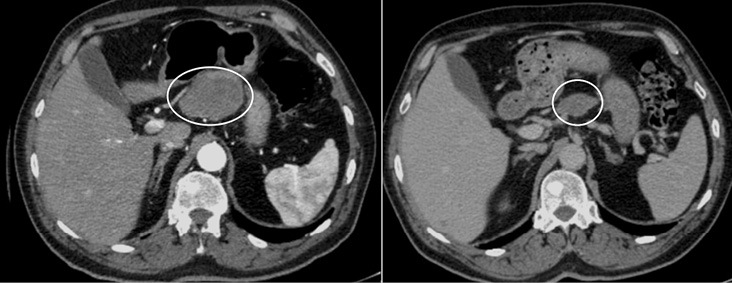

После 2 мес терапии абиратероном отмечалось прогрессирование в виде увеличения размера и количества метастатических очагов в печени, размеров абдоминальных и тазовых лимфатических узлов, появление метастатических очагов в поджелудочной железе, правом надпочечнике, парагастральных лимфатических узлах и развитие гидронефроза 2-й степени слева (рис. 6, 7).

Рис. 7. КТ органов брюшной полости после 2 мес лечения. Отмечается появление опухолевого очага в хвосте поджелудочной железы (левый верхний слайд), поражение парагастральных лимфоузлов (левый нижний слайд), увеличение размеров конгломерата подвздошных лимфоузлов со сдавлением левого мочеточника (правый верхний слайд), формирование гидронефроза слева с расширением чашечно-лоханочной системы (правый нижний слайд).